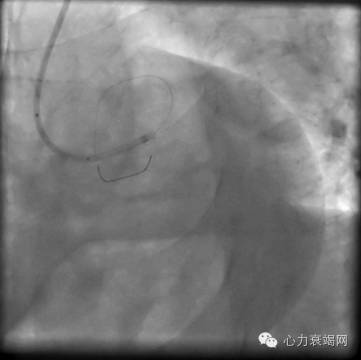

急诊PCI

冠脉造影示:LAD自口部闭塞,LCX中段50-80狭窄,RCA近段80%狭窄

PCI:LAD近段置入3.0*23支架1枚

影像学资料